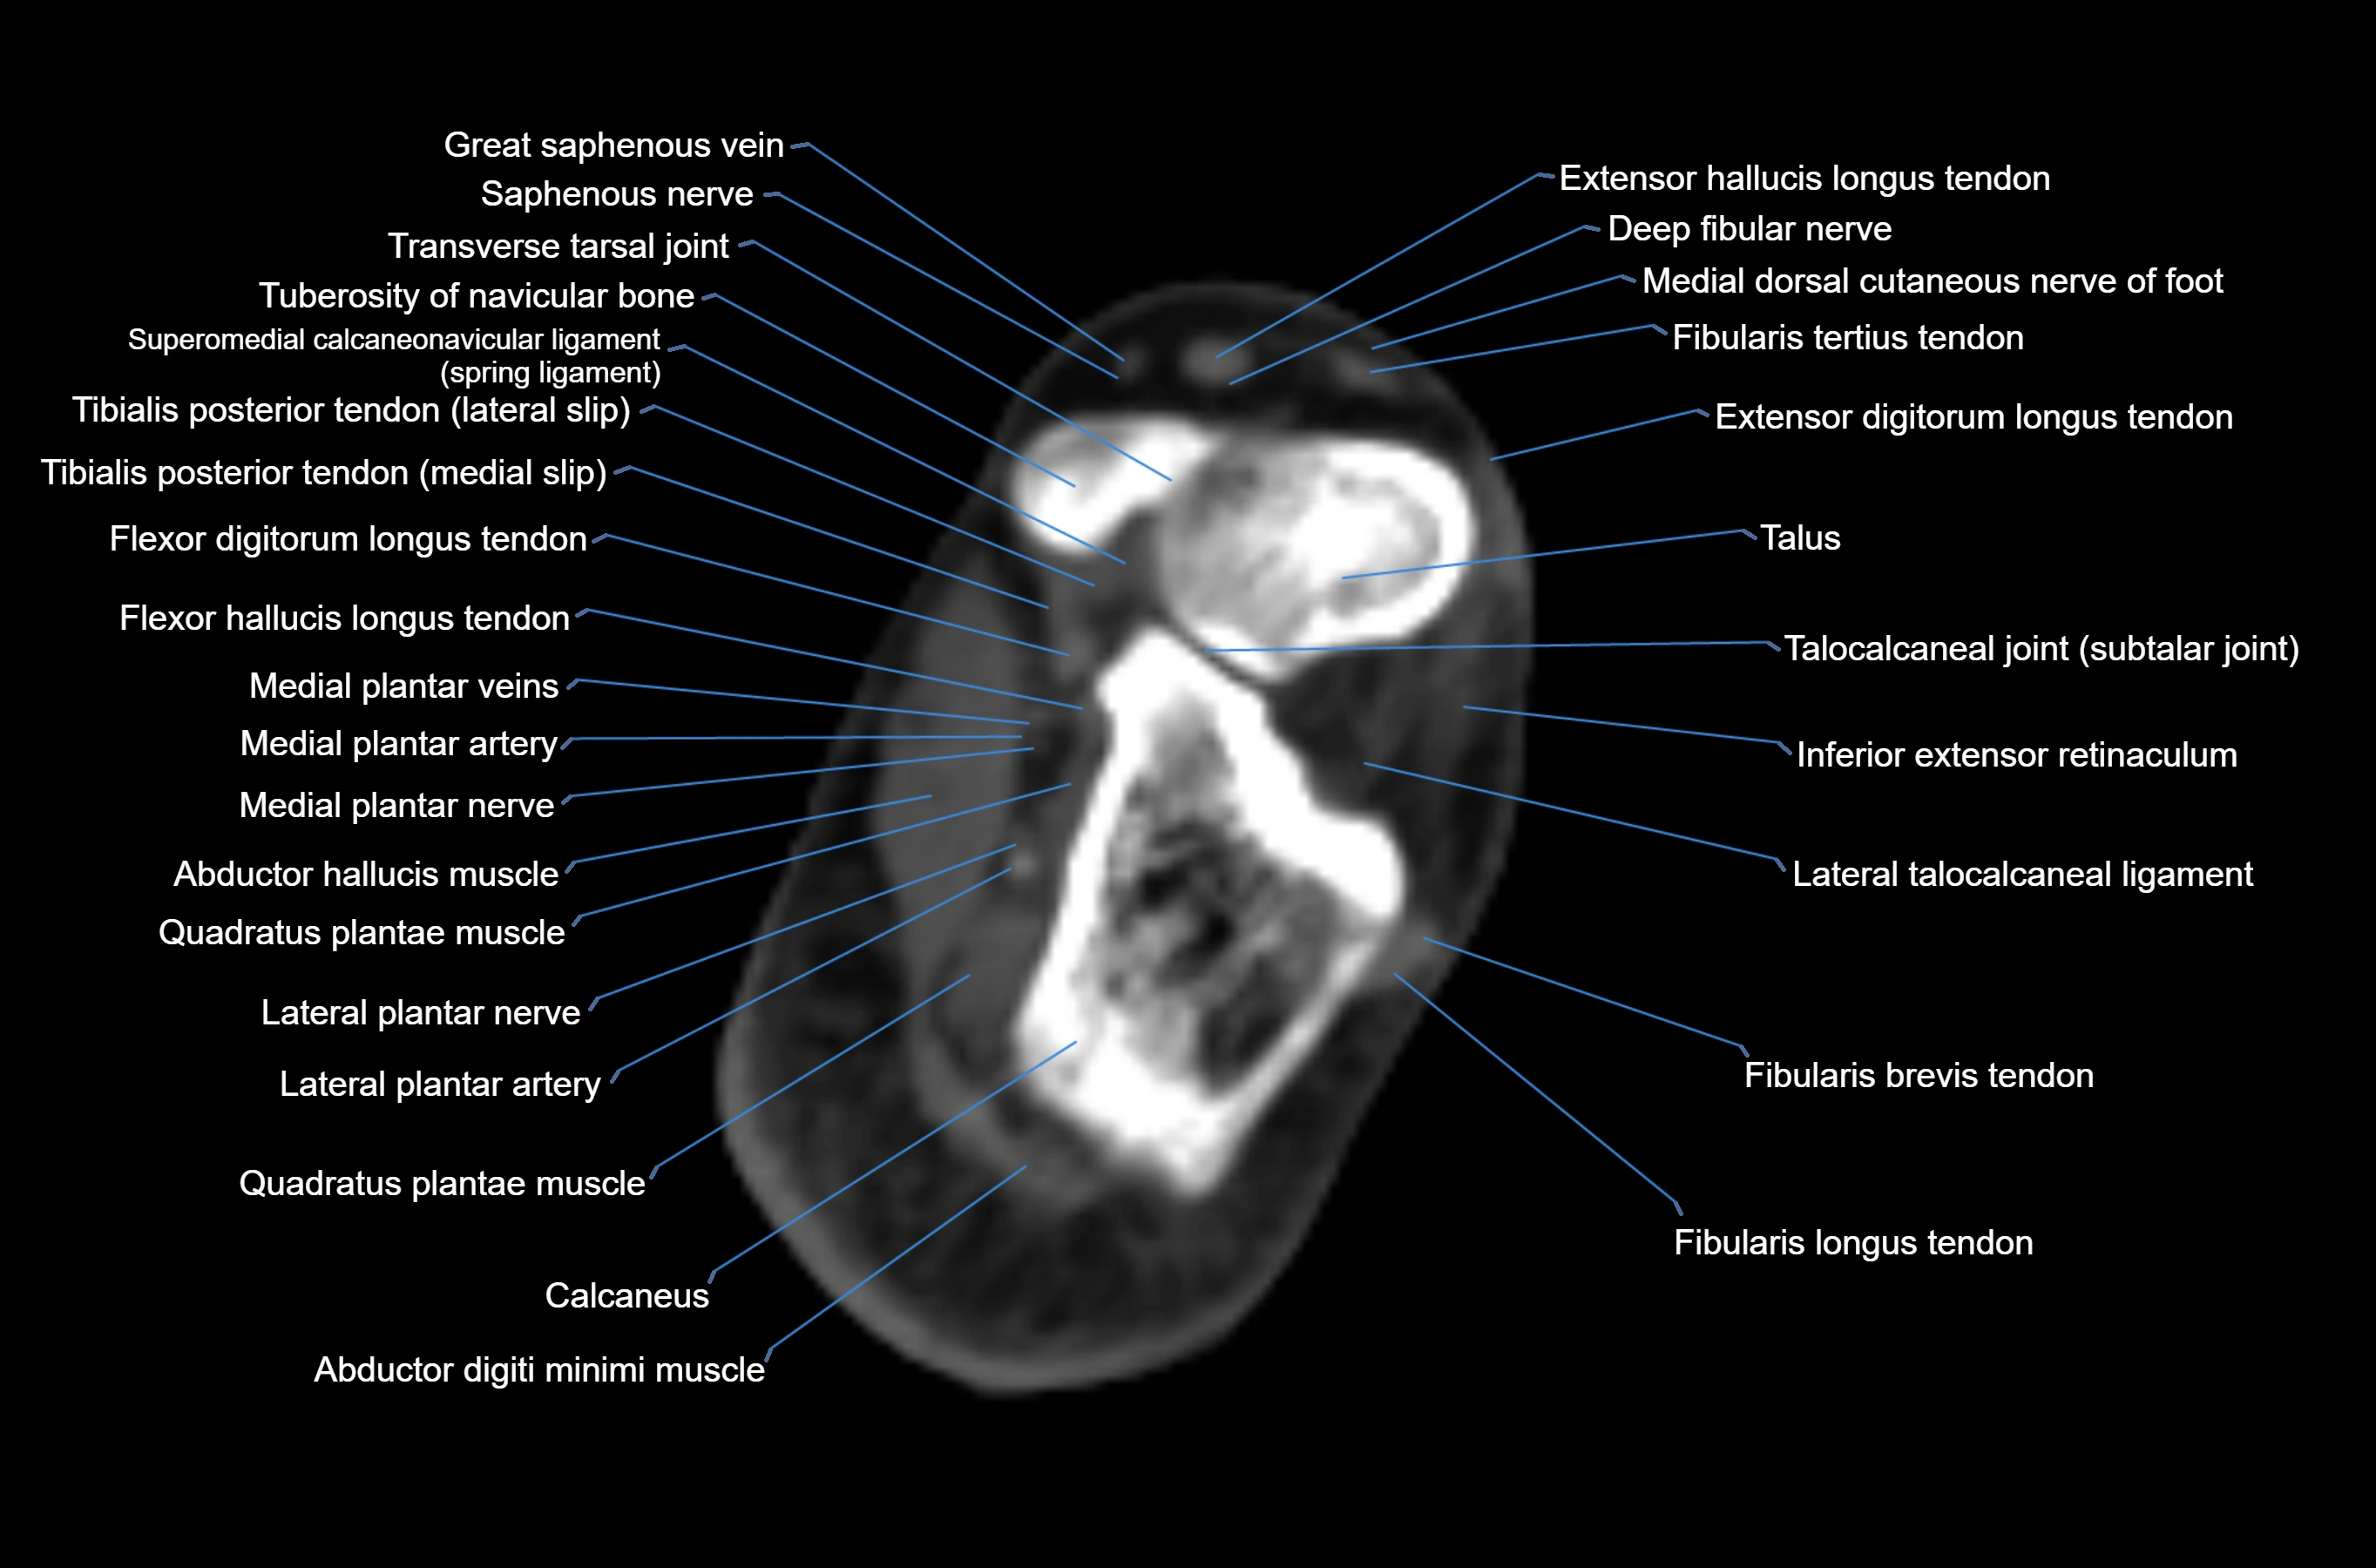

- Abductor digiti minimi muscle

- Abductor hallucis muscle

- Calcaneus

- Deep fibular nerve

- Extensor digitorum longus tendon

- Extensor hallucis longus tendon

- Fibularis brevis tendon

- Fibularis longus tendon

- Fibularis tertius tendon

- Flexor digitorum longus tendon

- Flexor hallucis longus tendon

- Inferior extensor retinaculum

- Lateral plantar nerve

- Lateral talocalcaneal ligament

- Quadratus plantae muscle

- Small saphenous vein

- Talus

- Transverse tarsal joint

- Tuberosity of navicular bone

- great saphenous vein